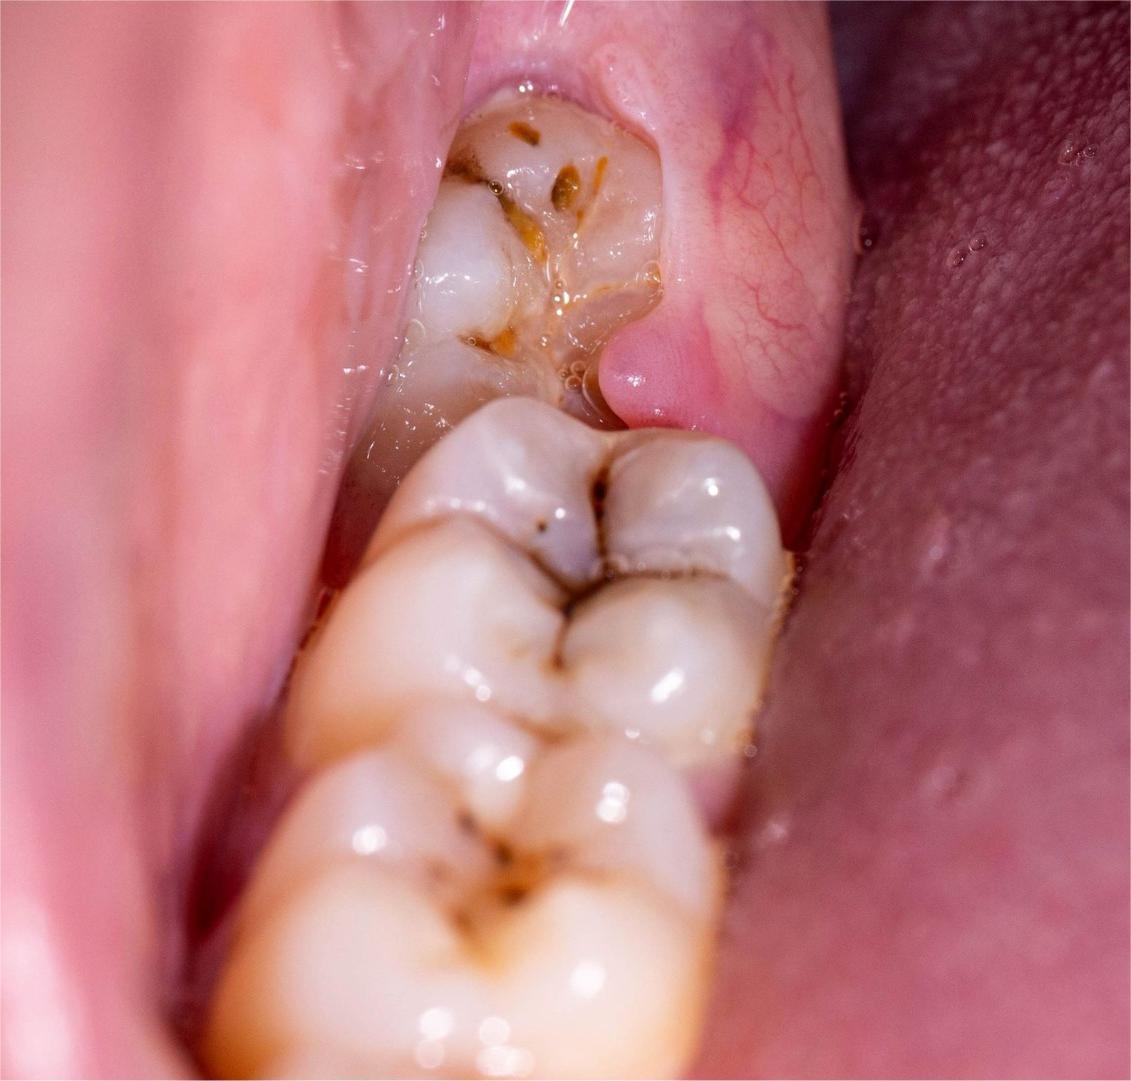

Is Root Canal Treatment painful at your clinic?

At Dr. Ritika's EndoElite Implant, Laser & Aesthetic Centre, Root Canal Treatment is performed using modern rotary instruments and digital imaging. The procedure is safe, comfortable, and almost painless under local anesthesia.